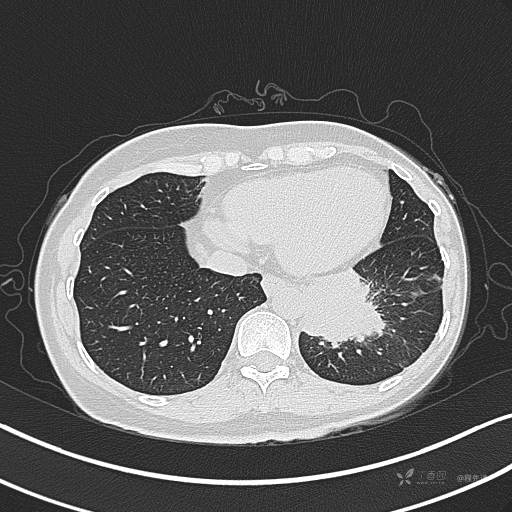

CT平扫

肺窗